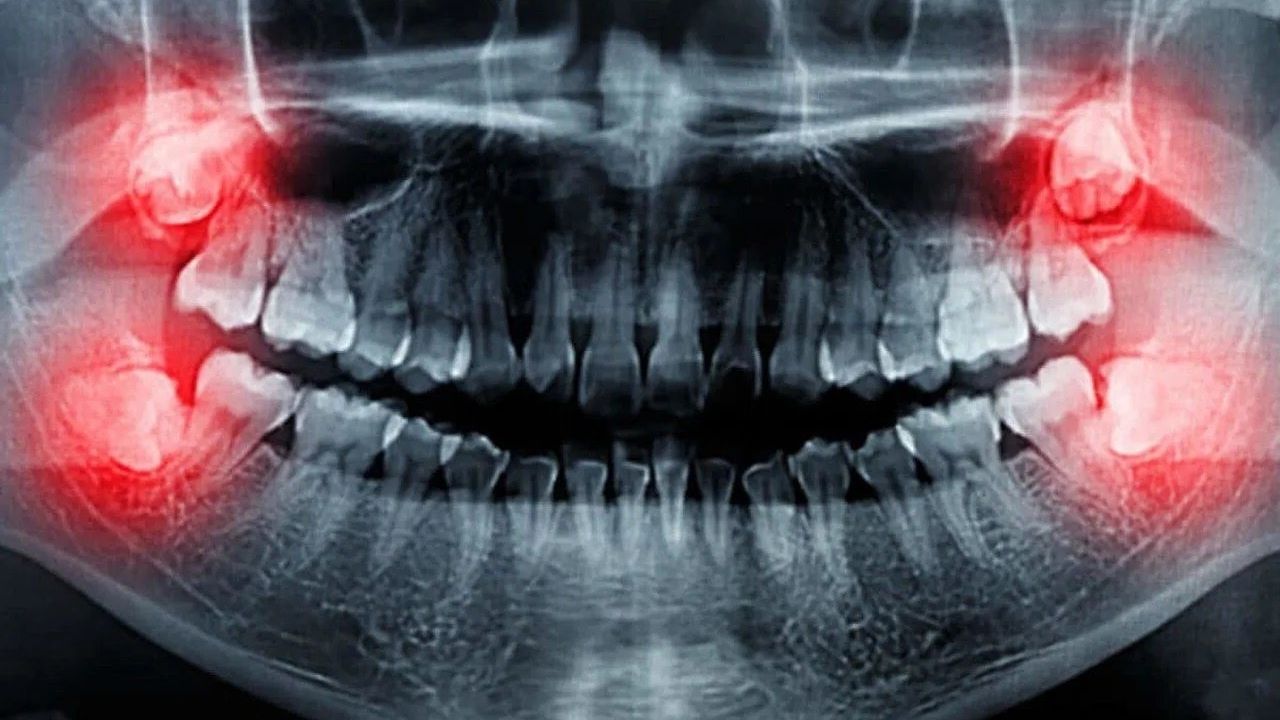

Çenenin arkasında, ergenlik döneminde (17-25 yaşları arasında) çıkan üçüncü büyük azı dişleri olarak bilinen 20’lik dişler, genellikle alt ve üst çenede ikişer adet olmak üzere toplamda dört tane bulunur. Bazı kişilerde daha fazla 20’lik diş de gözlenebilir. Bu dişler, yer darlığı nedeniyle gömülü kalabilir veya ağrıya neden olarak ön dişlere baskı yapabilir.

Ne Zaman Çekilmelidir?

Diş hekiminiz, 20’lik dişlerin çekilmesi gerekip gerekmediğine karar verebilir. Aşağıdaki durumlarda dişin çekilmesi önerilir:

- Diş çürümesi

- Apse oluşumu (perikoronitis)

- Basınç ağrıları

- Ortodontik tedavi gereksinimi

- Kist oluşumları